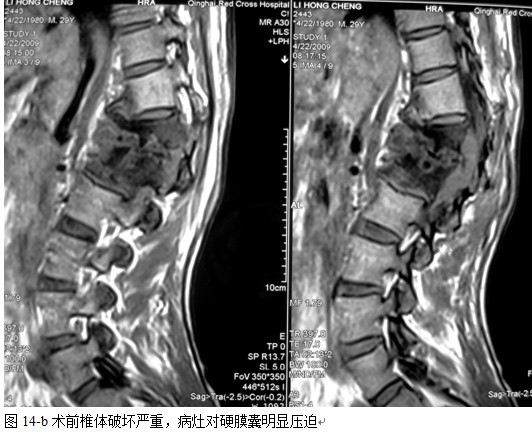

本组46例中男28 例,女18 例。年龄17~67岁,病程6 个月~7年,平均11.3 个月。本组患者均为 L1~S1腰段结核。病灶累及2 个椎体31例(L1-2 6例, L2-3 8例,L3-4 10例,L4-5 5例,L5-S1 2例),3 个或3 个以上椎体15例。合并腰大肌脓肿23列,所有患者均有腰背部疼痛,活动受限,双下肢感觉麻木19例,会阴部感觉减退12例,双下肢肌力减弱12例,腱反射减弱12例,术前后凸角(Cobb 角) <30°者12例, 30°~60°者28 例, >60°者6 例,Cobb角平均32.3°4例患者是二次手术。术前均行X线片、CT或者MRI检查。术后病理检查确诊为脊柱结核。

本组手术用时间3~4h , 平均3.5h 。术中出血300~500ml , 平均约350ml 。术后症状完全缓解,无神经功能障碍加重等并发症,1例营养差的老年患者伤口出现窦道,1例因肝功能差,术后未口服抗痨药,伤口出现窦道,经换药后二期愈合,其余病例伤口均一期愈合。马尾神经受损的患者术后基本恢复正常。术后一周后凸角平均 5.4°后凸畸形平均矫正90%以上, 最终后凸角平均8.3°,后凸角度平均丢失4.2°。随访3个月有87%(40/46)有骨痂形成,6个月91.3%(42/46)明显骨性愈合(见图),其余4例9-12个月内愈合,随访时间3-32个月,平均11个月,46例患者中2例在术后2个月和3个月时背部形成脓肿,换药后治愈。2例出院1月后并发结核性脑膜炎,治疗后好转。1例因椎弓根钉偏外,刺激神经根,5个月后从侧方脱出,疼痛加重,因前后路植骨完全愈合,取出后症状完全缓解。

中国学者金大地[22]等采用一期前路病灶清除植骨前路钢板固定治疗腰椎结核,平均18°的后凸畸形得以矫正,Mukhtar[23] AM等采用前路病灶清除植骨分期或同期后路固定治疗腰椎结核22例,术后后凸畸形矫正度数平均为27°。从我们的随访结果看,术后后凸畸形平均矫正度数为26.9°,后凸畸形平均矫正90%以上, 6个月-49个月后随访,后凸角度平均丢失4.2°。本术式也适用于结核所引起的弹性差的后凸畸形,对于病灶纤维化或骨化的非弹性后凸畸形,后路固定后,先行前路病灶、纤维化或骨化切除、松解,逐步刮除病灶、逐步撑开,达到畸形矫正和植骨的目的。